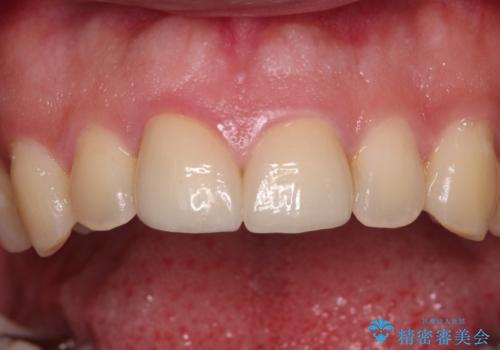

しかしながら、補綴治療後間もなく再度自転車事故に遭い、追加1本の計3本を損傷する事態となりました。

再度損傷した3本は完全に失活した状態であったため、速やかに根管治療を行い、オールセラミッククラウンにて補綴治療を行うこととしました。

歯が欠けるほどの強い衝撃を受けると、歯根が溶けてしまう外部吸収という現象を起こすことがあるため、補綴治療後しばらく様子を見ておりましたが、何と三度自転車事故に遭いかけてしまいました。